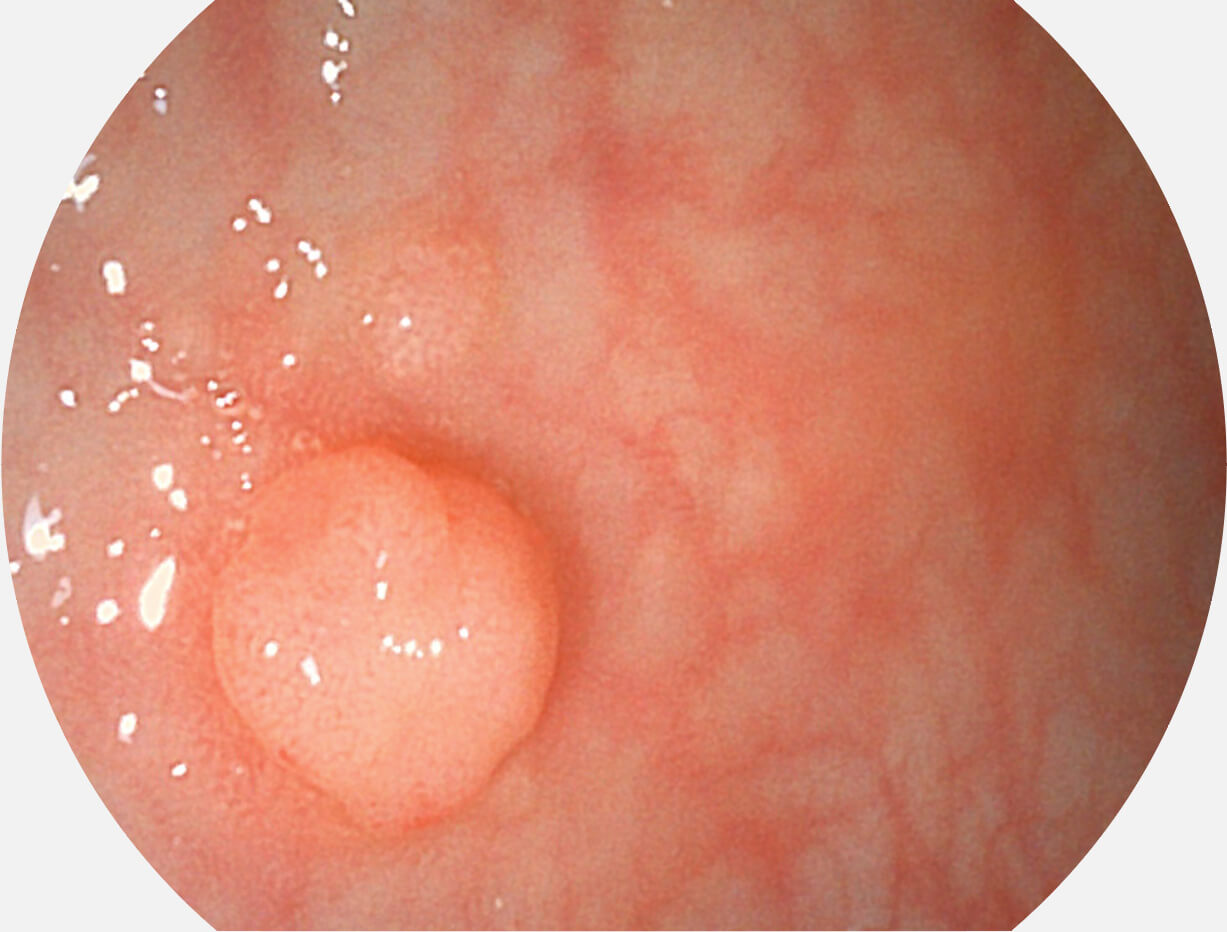

• 白光圖像 SFI圖像